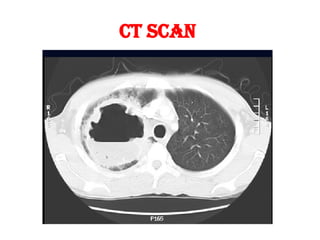

 CT Scan

CT SCAN